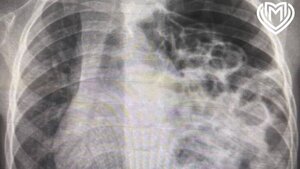

Лилли поступила в клинику с подозрением на грипп, но при обследовании медики обнаружили у нее менингококковую септицемию. Эта бактериальная инфекция вызвала септический шок и остановку сердца.

Девушка впала в кому на две недели. Из-за нарушения кровообращения медикам пришлось ампутировать Лилли руки по локти и ноги выше колена.